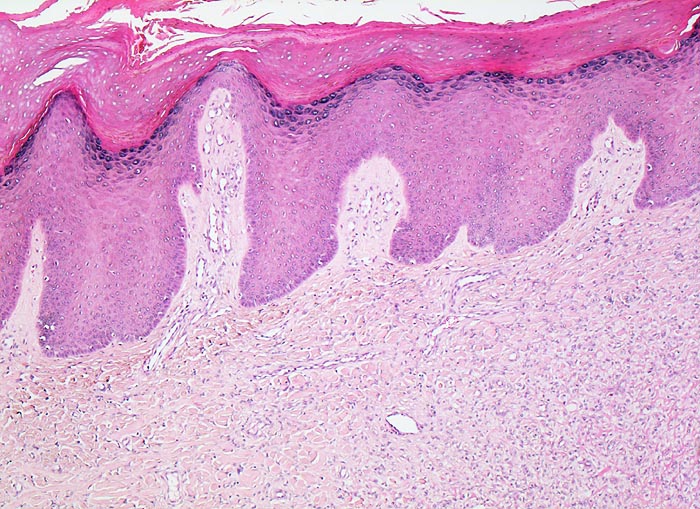

Die Epidermis über dem dermal lokalisierten Tumor zeigt eine Hyperplasie (> 7793) oftmals mit basaler Hyperpigmentierung PathoPic 7803. Histologisch besteht das Histiozytom aus einem Spektrum von Zelltypen mit Merkmalen von dermal dendritischen Zellen, (Myo)fibroblasten und Histiozyten. Zusätzlich können Entzündungszellen, fettspeichernde Tumorzellen mit schaumigem Zytoplasma, eisenpigment (Hämosiderin) speichernde Tumorzellen (> 7718) oder mehrkernige Riesenzellen vorhanden sein. Charakteristisch ist eine wirblige/sternförmige Anordnung von Spindelzellen und Kollagenfasern (=storiformes Wachstumsmuster). Kollagengehalt (> 219) und Zellgehalt (> 3967) sind von Tumor zu Tumor sehr unterschiedlich. Frühe Läsionen sind zell- und gefässreich, spätere zeigen eine vermehrte Fibrosierung und als Folge von Einblutungen Ansammlungen von lipid- und pigmentspeichernden Tumorzellen. Histiozytome können sehr zellreich (> 3968) oder sehr zellarm sein. Sehr charakteristisch ist die unscharfe Begrenzung des Tumors zum dermalen Bindegewebe mit Einschluss kompakter Kollagenfasern innerhalb des Tumors und Ausbreitung von einzelnen Tumorzellen zwischen die tumorangrenzenden Kollagenfasern.

• Epidermishyperplasie (Akanthose) und Hyperpigmentierung der basalen Keratinozyten über dem Tumor.

• Unscharf begrenzter dermaler Tumor ohne direkten Kontakt zur Epidermis.

• Tumor bestehend aus spindeligen (myo)fibroblastären Zellen mit länglichen Kernen in unregelmässiger Anordnung (Zellen mit unterschiedlicher Ausrichtung zueinander), mit storiformer (sternförmig/wirbelförmig) oder faszikulärer (parallel ausgerichtete Zellbündel) Architektur.

• Die charakteristischen Veränderungen der Epidermis helfen bei der manchmal schwierigen Abgrenzung des fibrösen Histiozytoms von anderen dermalen Hauttumoren. Deshalb sollte nach Möglichkeit die Epidermis mitexzidiert werden.